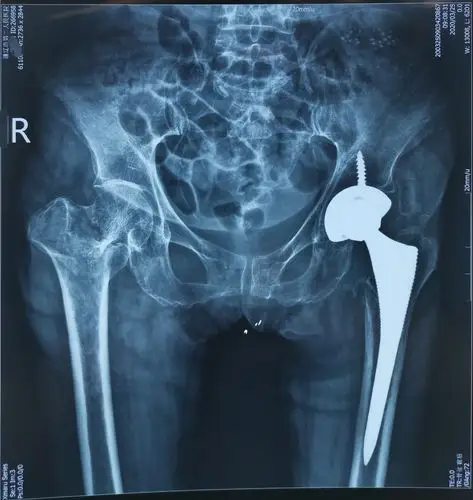

73岁股骨近端粉碎性骨折人工股骨头置换一例

新年一例股骨近端粉碎性骨折的手术治疗!